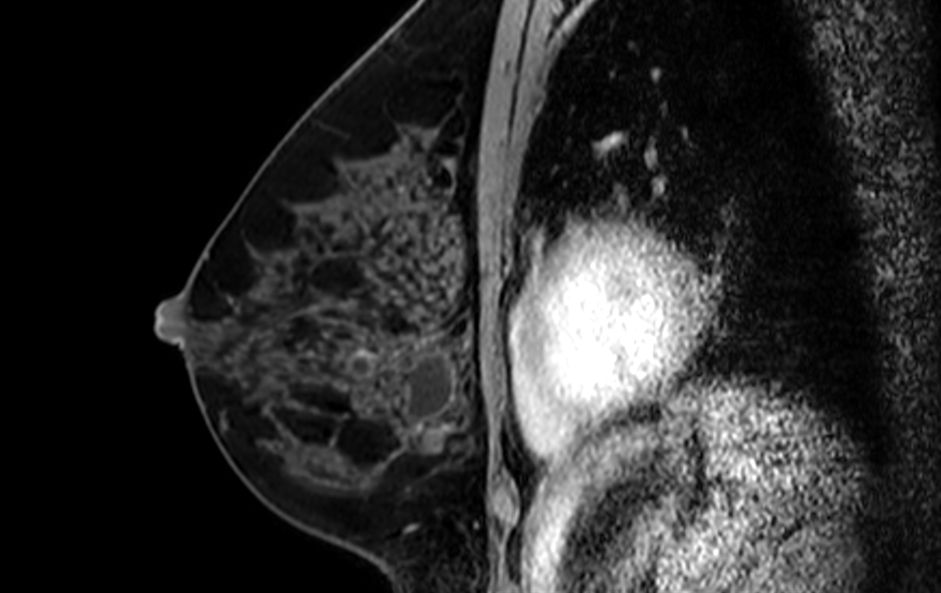

Axial 3D T2w BreastVIEW

3D T2w BreastVIEW (coronal reformat)

3D T2w BreastVIEW (sagital reformat)

3D Breast imaging lets you acquire high resolution data in multiple directions, including oblique, in one scan helping you enhance your confidence when diagnosing lesions. 4D FreeBreathing provides dynamic information with a high temporal resolution, allowing contrast-enhanced MRI breast studies.